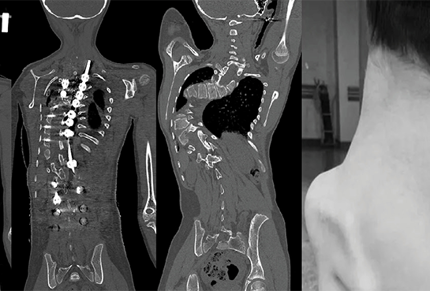

3D Printing Supports Treatment for Dorsal Scoliosis

Aakash Healthcare Uses Stratasys’ J5 MediJet to create 3D Printed Pre-Surgical Model and Jigs to Correct Scoliosis Deformity